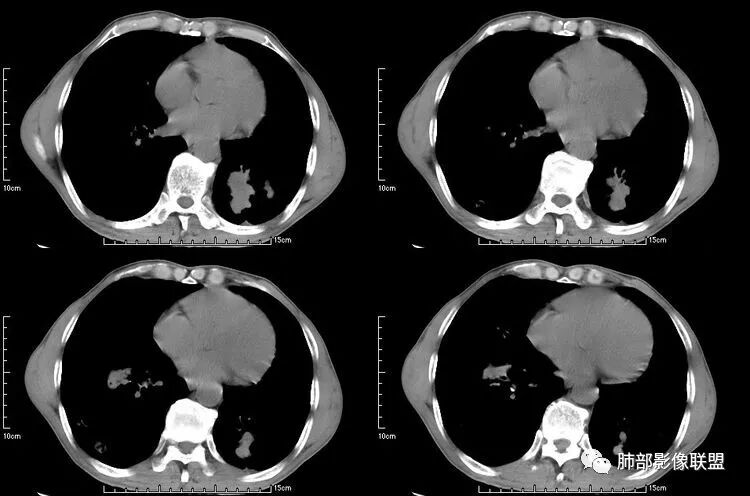

患者老年男性,咳嗽、咳痰、痰中带血伴胸闷2月余。长期大量吸烟史。查肝肾功能、血糖、血脂、心肌酶、电解质、血沉、C反应蛋白、抗“O”、类风湿因子、抗核抗体谱无明显异常。肿瘤标志物提示NSE、CYFRA21-1稍升高。胸部CT:肺气肿背景,左肺下叶后基底段不规则肿块影,见支气管截断,内见大片状低密度区及部分血管影,增强轻度强化,远端空洞形成。双肺多发不规则实性结节影、见毛刺、胸膜牵拉及血管集束,结节内见空洞形成,部分可见血管影,多位于胸膜下。双肺见多发肺大泡。综合考虑左下肺恶性病变并双肺转移。鳞癌或淋巴瘤可能。鉴别血管炎性病变及真菌感染。

左肺下叶团块病灶,有明显张力,增强后病灶内部有可疑延迟强化,看不清楚病灶与支气管的关系,应该支气管受压阻塞了,双肺多发胸膜下小结节,病灶小结节病灶有平行胸膜生长的表现,部分小结节厚壁,部分薄壁,,还有一部分有内容物,这需要两元论,左肺下叶肺癌(腺癌)伴转移,同时合并真菌感染。

液化,而不像坏死,是有强化的;这个里面似有液平。说明里面有分泌粘液?

无发热,其他慢性细菌先不考虑,有的低毒的,但是结节形态还是比较不规则的,分布也是比较随机,更像原发病灶。真菌方面,结节没有融合,坏死也是液化坏死,不符合隐球菌,曲霉不符合IPA,慢性吸入的也少见。结核没有树丫,不考虑。鉴别主要是GPA,和肺癌。GPA不支持点是皮肤,肾脏没有累及,ANCA不支持。。。肺癌主要是腺癌和鳞癌转移。比较支持的是淋巴结肿大,和左下肺的主病灶,支气管堵塞和异常强化。还有分叶,局部膨隆。可以建议支气管镜检测。

本病例左肺下叶肿块,有深分叶、毛刺、胸膜牵拉凹陷、支气管截断及纵隔内淋巴结肿大等征象,都均支持病灶为恶性,如腺癌,而且叶间裂的多发结节也提示是腺癌来源可能大;双肺多发结节、肿块,大部分病灶有分叶、毛刺及胸膜凹陷的恶性征象,与原发肿瘤本身的性质有关,所以应该与左肺下叶肿块同源,而且双肺多发病灶内空洞也具有多样性;